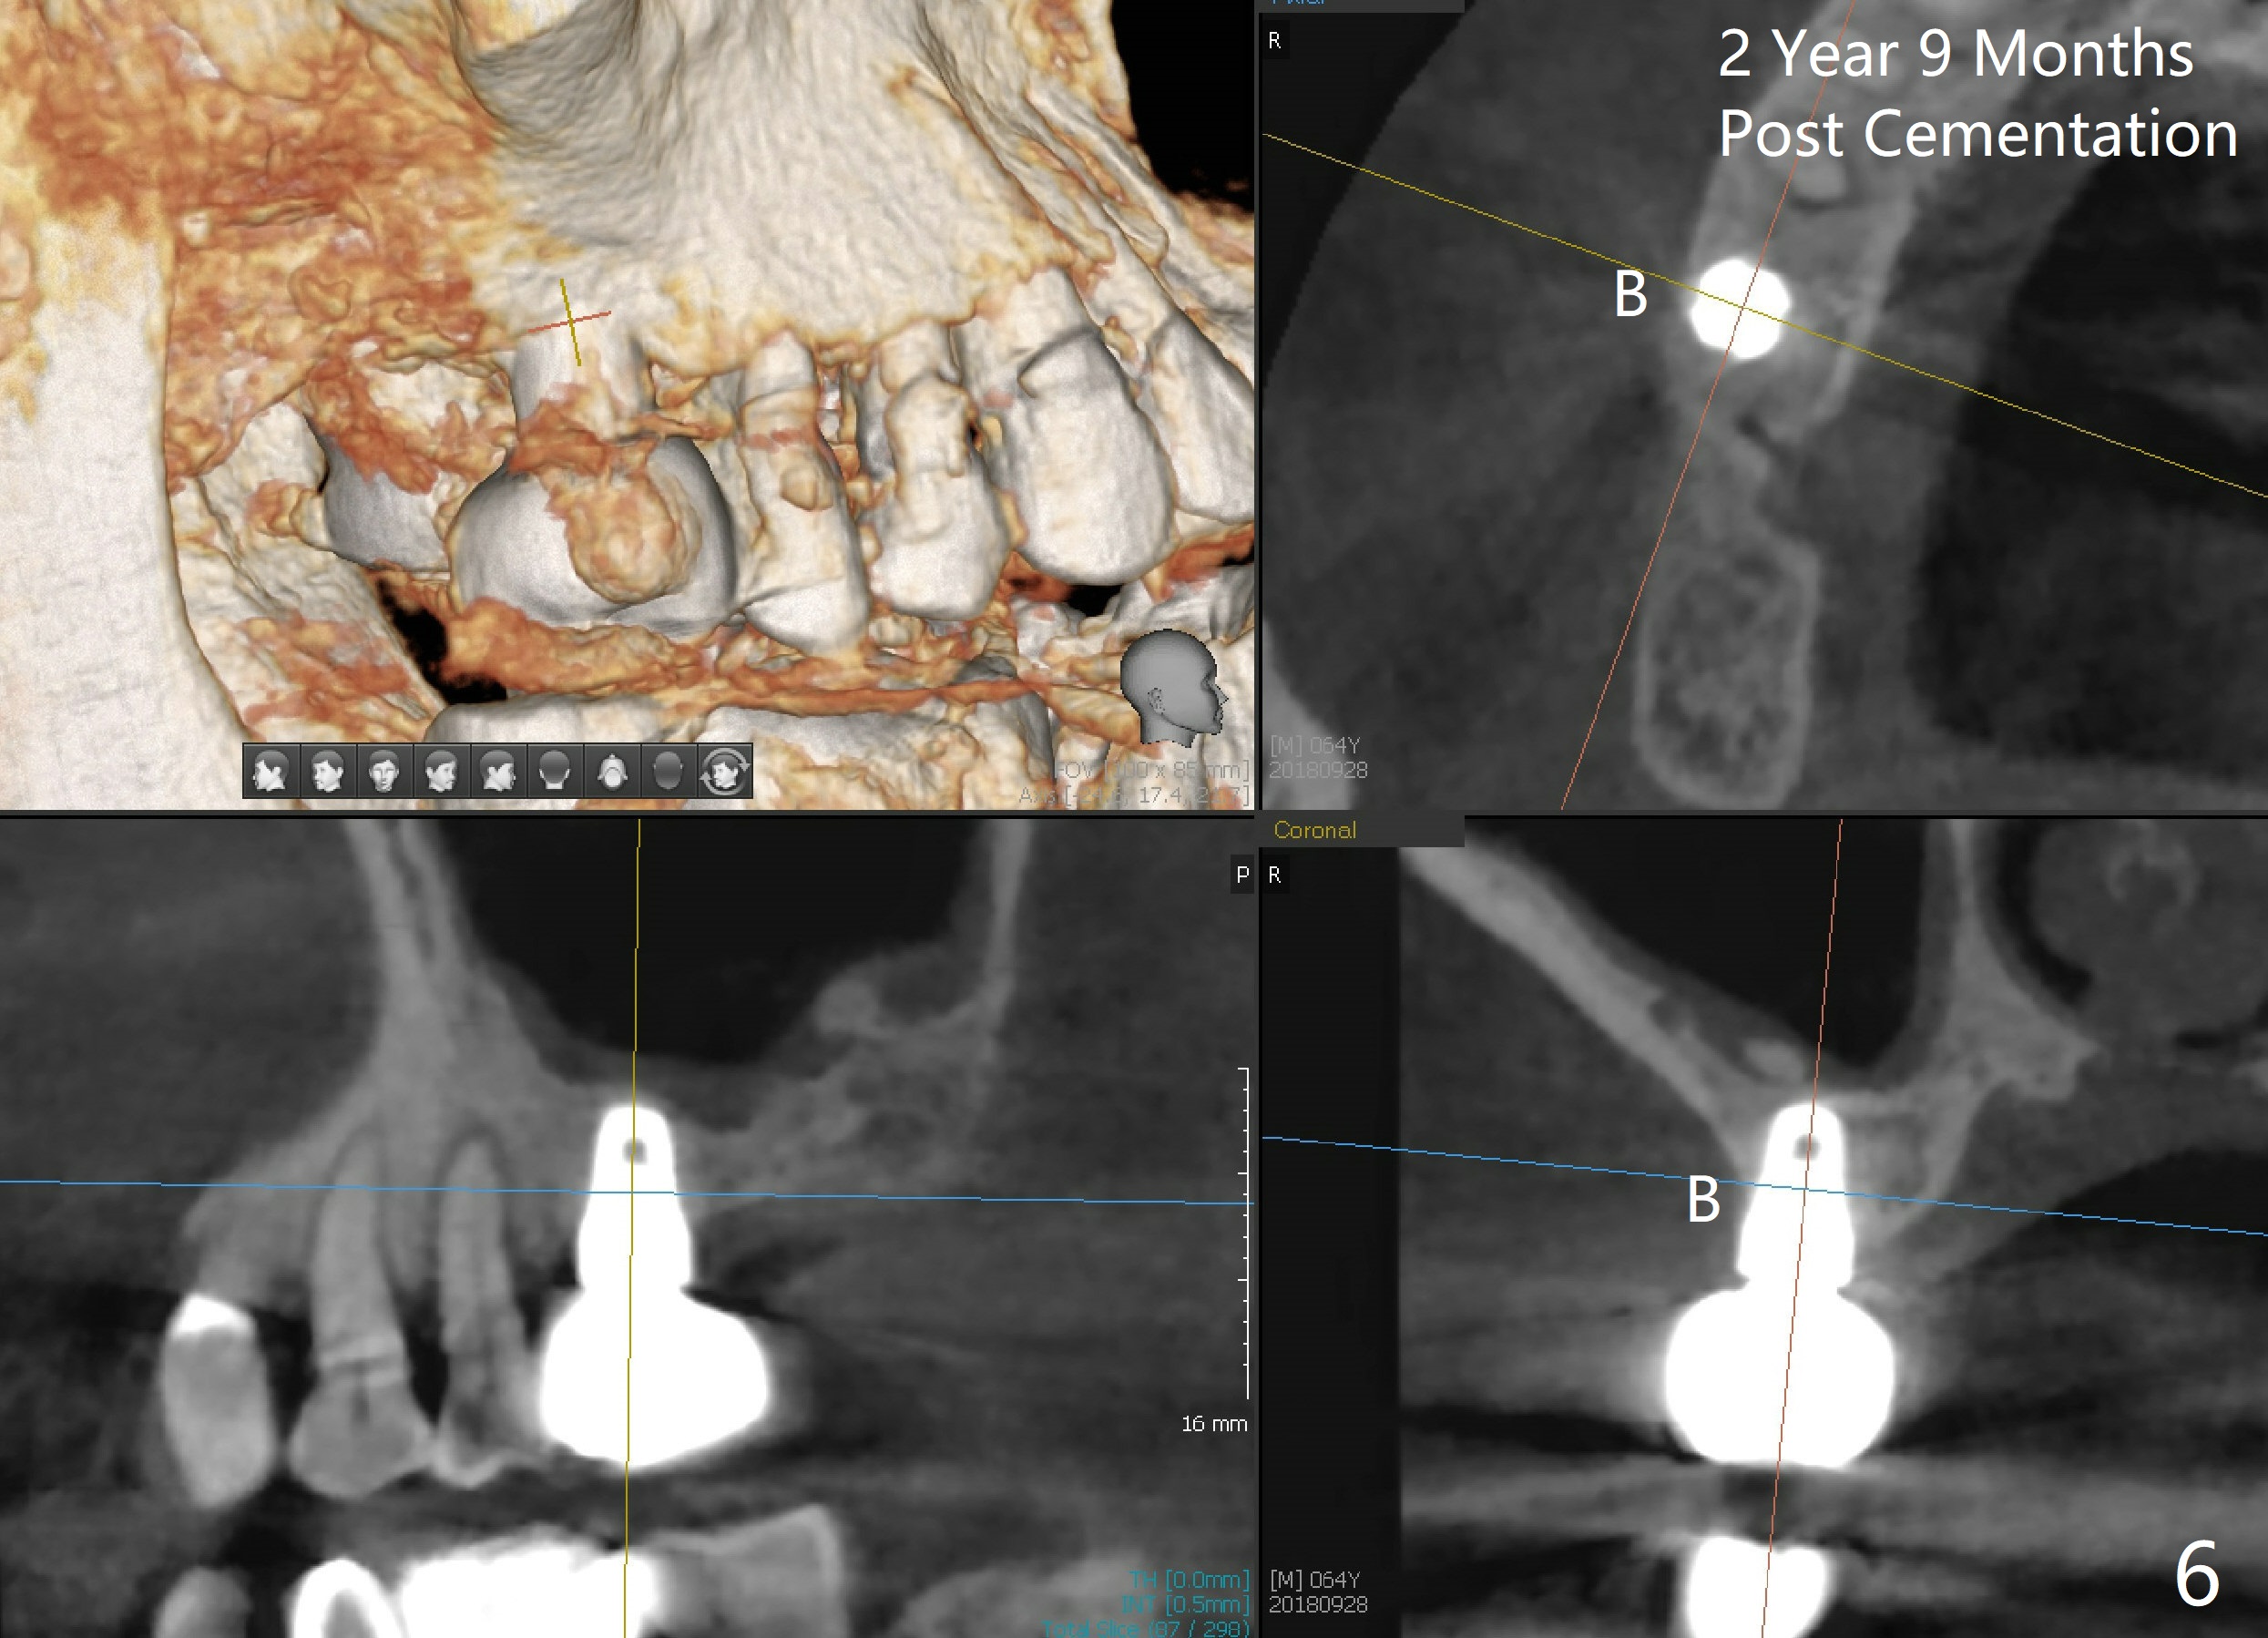

Bone expander kit is planned for for the case at the site of #3 with apparently normal buccolingual width (Fig.1). Bone density proves to be not low intraoperatively. First, when the 1.6 mm pilot drill is being used, the bone does not feel soft. Second, the first expander (2.6 mm, Fig.2 E) cannot be driven into the osteotomy (following the pilot drill) unless 2.5 mm reamer is used. Third, when larger expanders (until 3.8 mm) and 5x11 mm tap (Fig.3 T) are being used, the distobuccal plate starts to crack, although insertion torque of 5.3x8 mm implant is >50 Ncm (Fig.4). Using bone expanders is time consuming. In brief, when the buccolingual width is within normal limit and bone density is not low, traditional osteotomy should be adopted. It is better to use reamers to collect autogentous bone at the same time. The bone can be put back later into the osteotomy for sinus lift. Another drawback of this case is that the implant is not placed deep enough (Fig.5: 3 months postop). When a crown is cemented 1 year 4 months postop, the distal coronal portion of the implant is supragingival, although there is no infection.